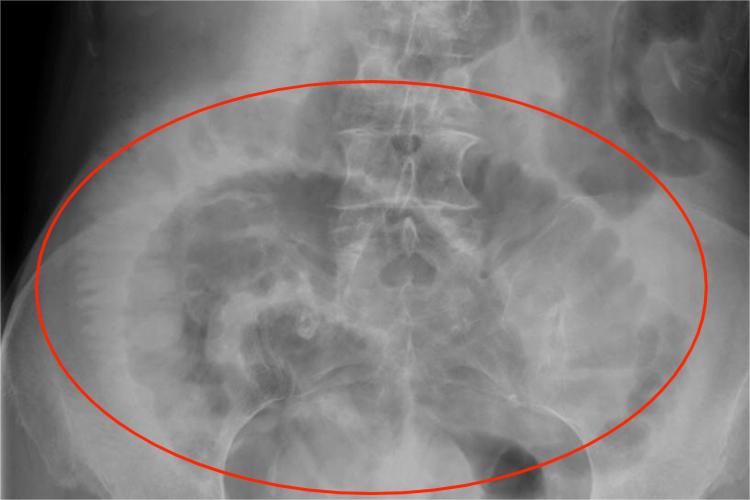

X线:立位检查可见肠腔内有多个液平面,液平面较短,肠腔内气柱高,同时还有小肠扩张积气,如单纯性小肠梗阻患者表现为积气肠曲舒展,肠管壁在气体衬托下,显示“鱼肋样”黏膜皱襞或皱襞减少。